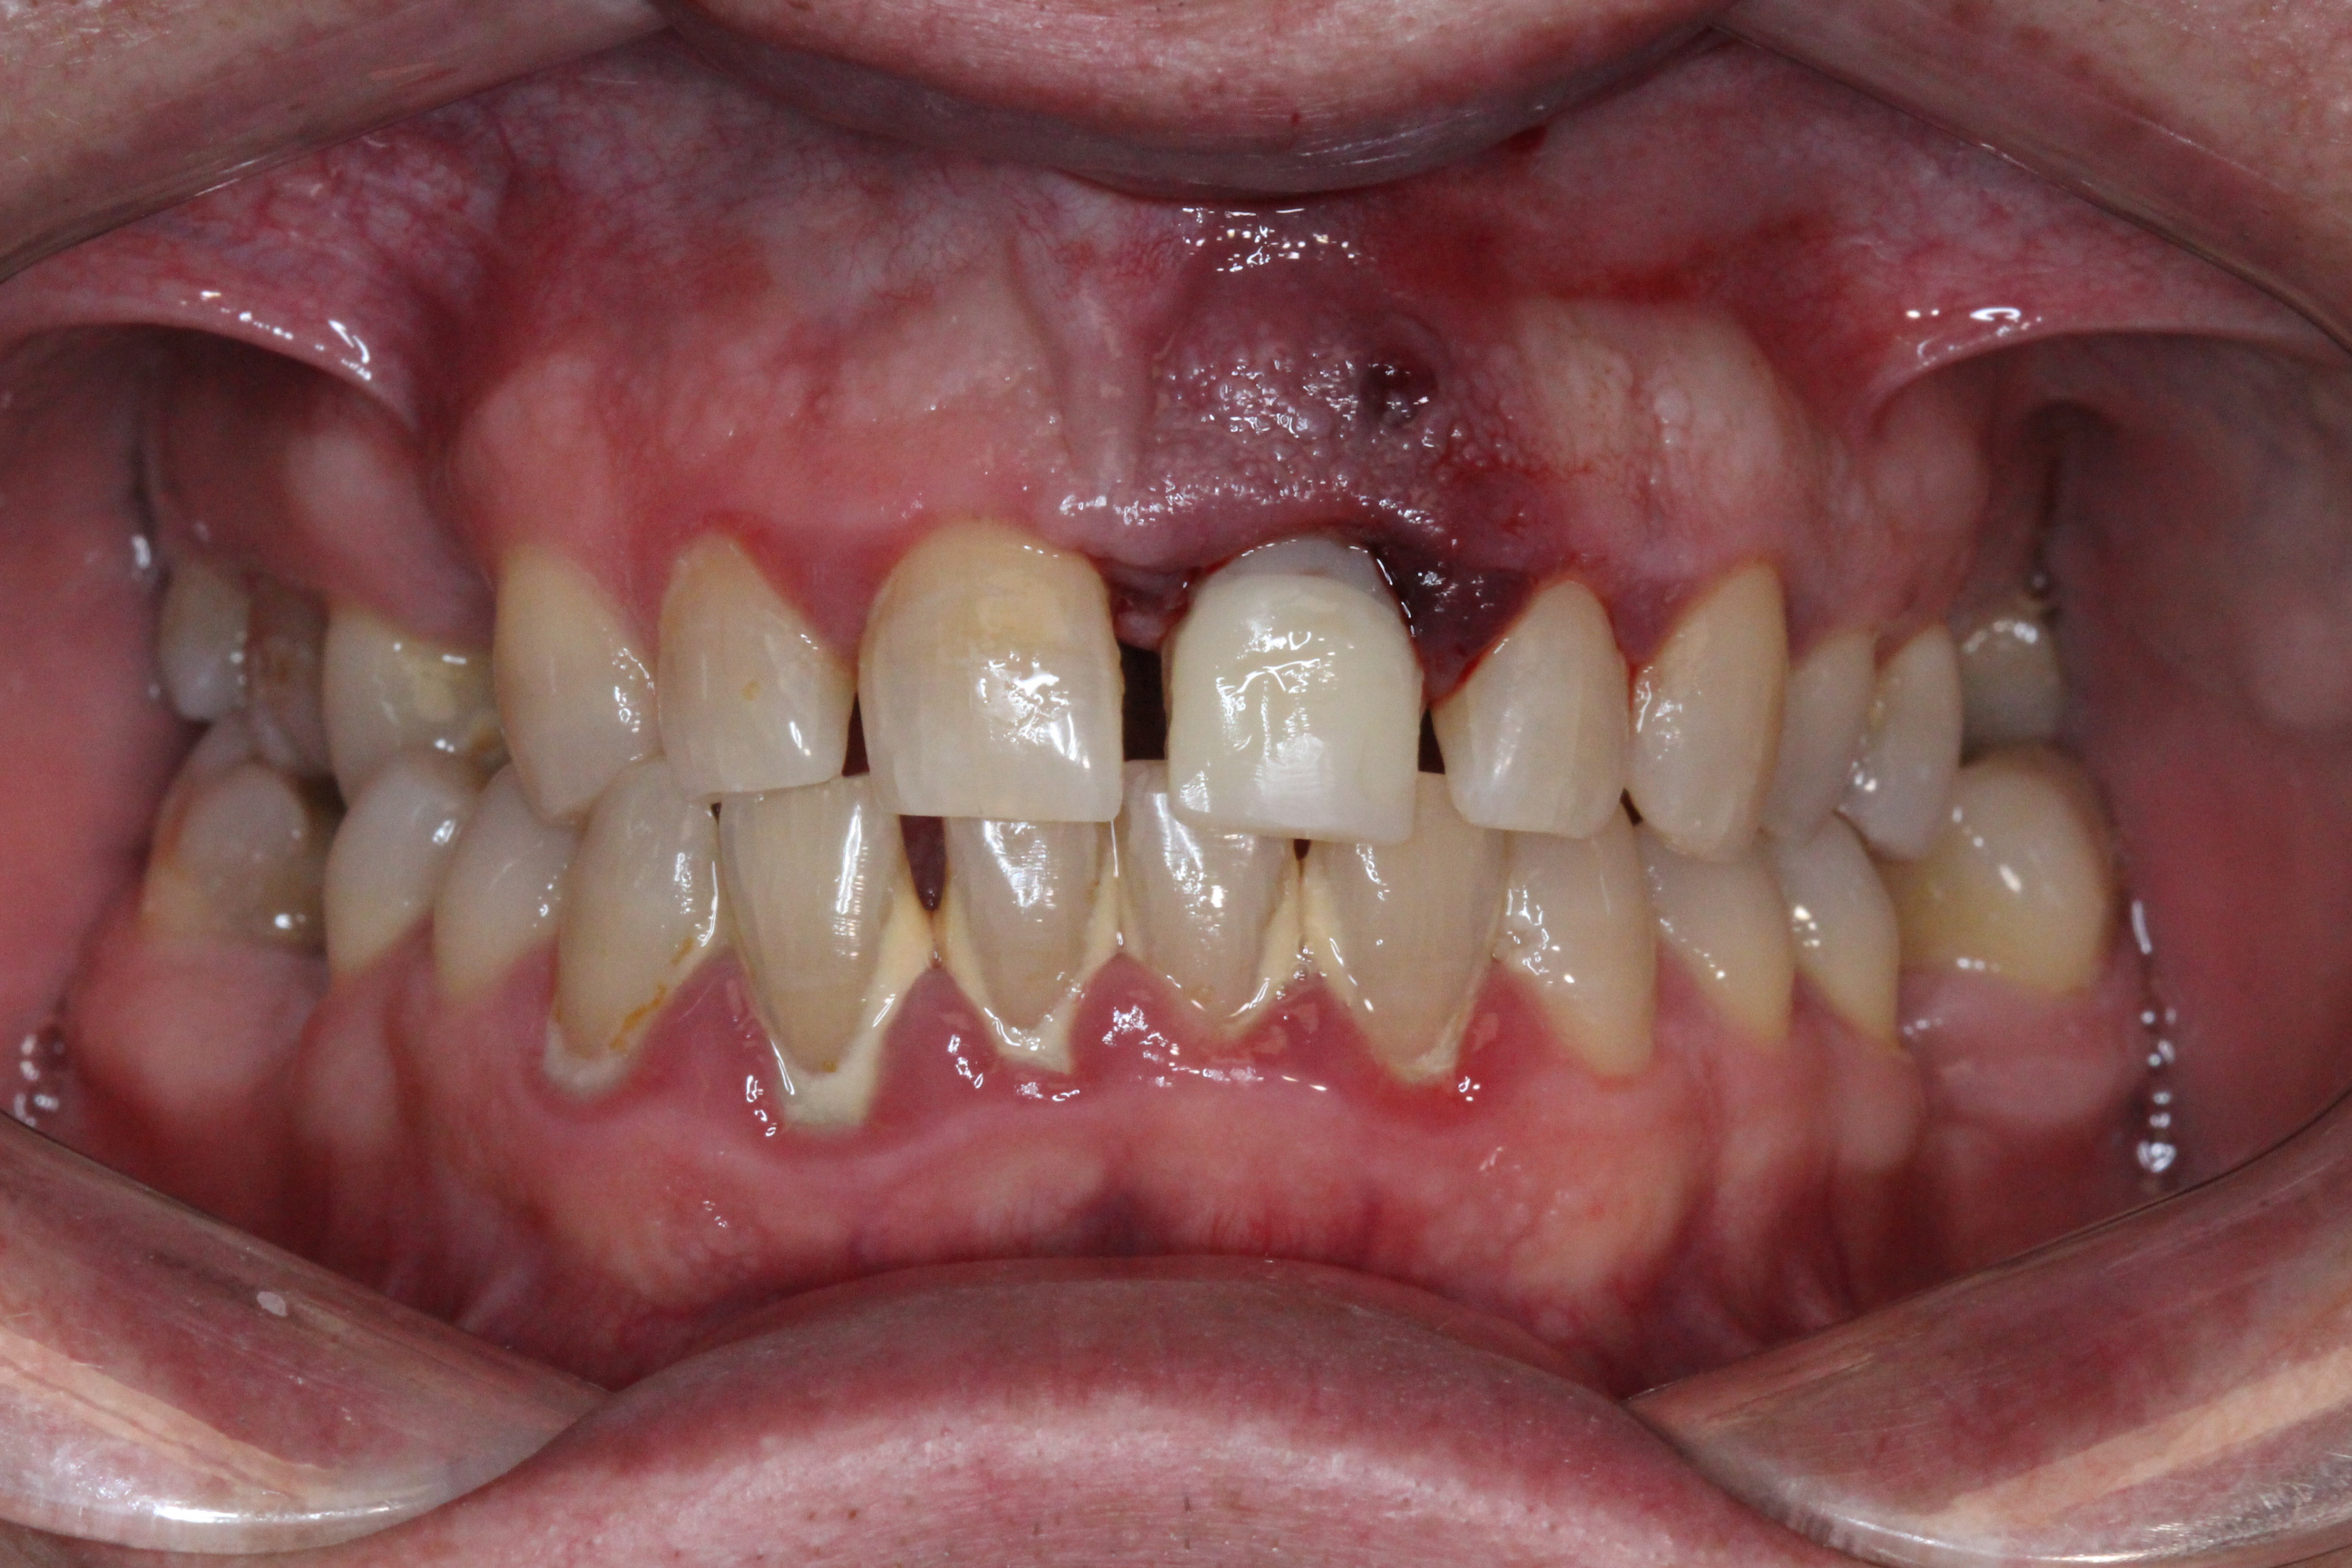

The patient left the clinic with a temporary crown on the day of surgery and was advised to follow a soft-food diet for the first month.

1 month post-op:

Prosthetic Phase

A digital impression was taken using a DSI scan body at fixture level with a Primescan intraoral scanner.

The temporary crown was replaced with a permanent zirconia crown supported by an individual custom titanium abutment.

The titanium abutment underwent anodization, an electrochemical process that thickens the titanium oxide layer to improve aesthetics, enhance soft tissue response, and reduce metallic shine in cases with thin mucosa.